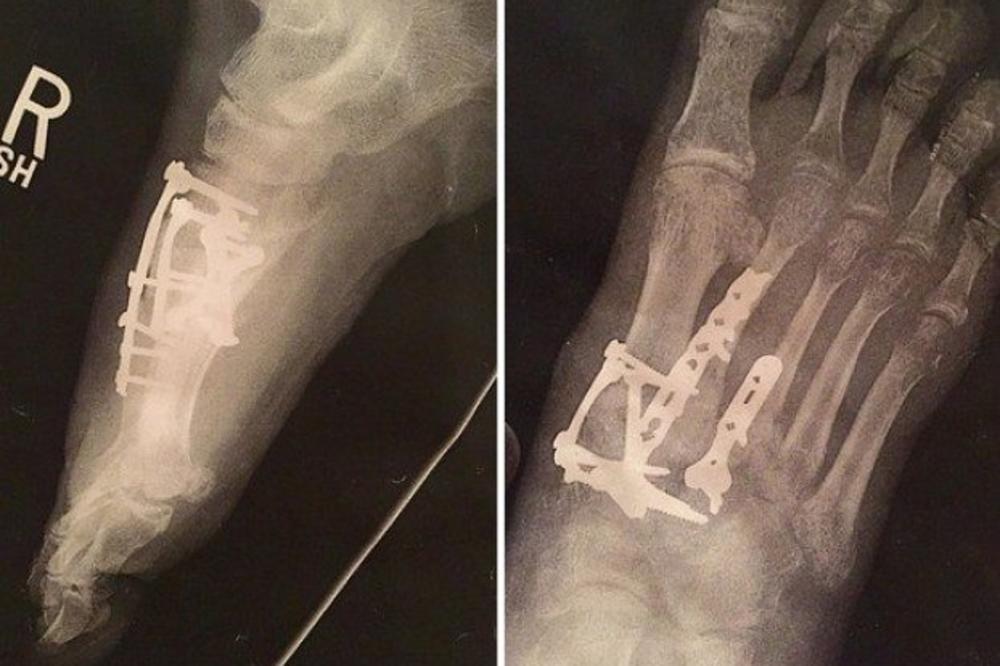

Međutim, nedavno je njegovo stopalo počelo da menja boje i užasno da svrbi.

Noga mu je oticala i bilo je gotovo nemoguće da navuče cipelu.

Jednoga dana, nešto neverovatno je izašlo na površinu kože…

Bila je to glava jednog od šrafa iz njegove noge! Nezgodna povreda i zaista neprijatan osećaj.